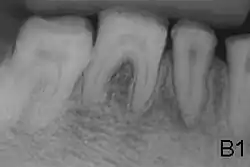

Radiografía de la dentadura de un paciente con amelogenesis imperfecta en la que se aprecia la falta de esmalte